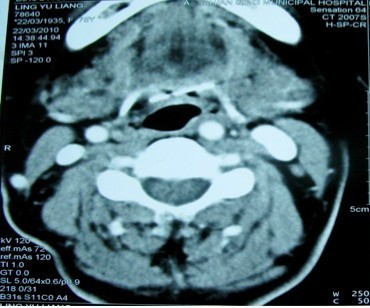

入院后全麻下行“直接喉镜下喉肿物活检术”,术中检查会厌谷未发现异物,取左侧会厌舌面粘膜溃疡组织送病检,术后病检示“(咽喉)炎性坏死物及粘膜慢性炎,鳞状上皮增生”。术后一周后患者又突感咽部剧烈疼痛,无发热,无呼吸困难,喉部检查见会厌无红肿,活检创面愈合良好,左侧杓会厌皱襞稍肿,行喉部CT检查示舌根稍上层面金属异物影,局部伪影形成,考虑金属异物。

诊断:颈部迁徙性异物 治疗:于局麻下行颈前舌骨上径路咽部异物取出术,沿颈部舌骨上缘皮肤横形切开,暴露舌骨,分离至右侧舌骨大角,取出长约2.5cm波浪形尖端锐利之细铁丝一根,术后抗炎止血治疗,患者一周后治愈出院。